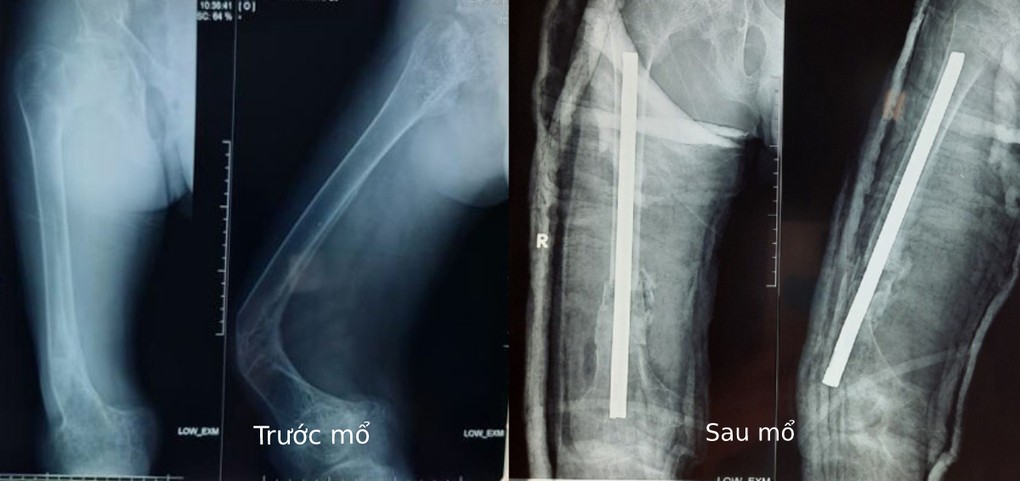

Xếp lại xương đùi cho chàng trai 'thủy tinh'

Y tế 24h - 17/10/2020

TP HCM - Nam thanh niên 20 tuổi, ngụ Bình Chánh, mắc bệnh xương thủy tinh, không may bị ngã làm gãy biến dạng đùi phải.